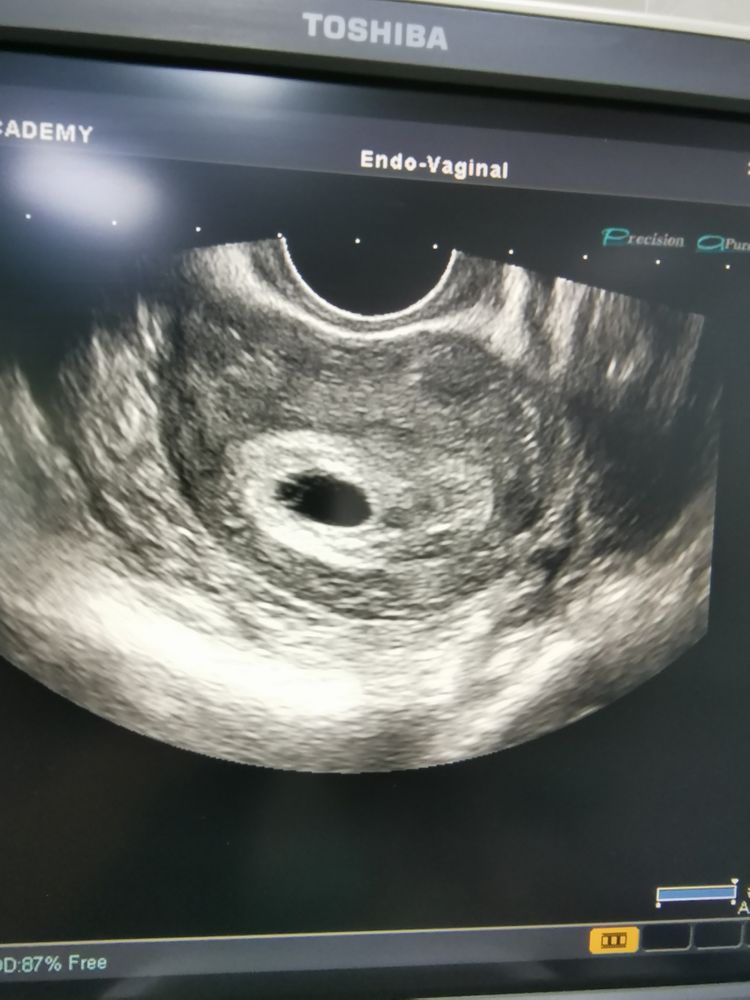

Узи, 5 недель, старый аппарат.

Изображение Начало шестой недели